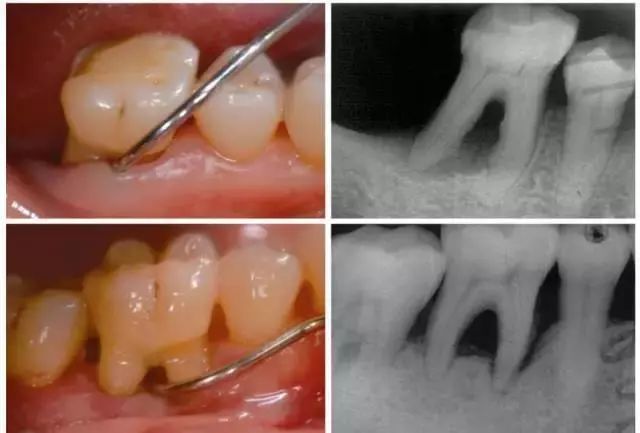

因为你看不见的地方是这样的↓↓↓

牙结石又分为「龈上结石」和「龈下结石」,龈上结石看得见,但是龈下的就没那么容易看得见了,也很难彻底清理,会刺激牙龈,造成牙龈发炎,糜烂,出血,加上牙周炎病人牙周袋较深,易堆积细菌,最后可能会导致牙齿脱落。

而且,一般常规的洗牙只能去除表面(龈上)的牙结石,而不能达到清洁牙齿的效果,想要彻底清除刺激物,就需要做深度清洁(深刮)。